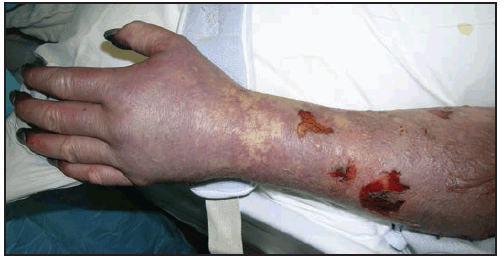

Long-term neurologic sequelae of RMSF include cognitive impairment; paraparesis; hearing loss; blindness; peripheral neuropathy; bowel and bladder incontinence; cerebellar, vestibular, and motor dysfunction; and speech disorders (7,110,121–124). These complications are observed most frequently in persons recovering from severe, life-threatening disease, often after lengthy hospitalizations, and are most likely the result of R. rickettsii-induced vasculopathy. Cutaneous necrosis and gangrene ( Figure 23) might result in amputation of digits or limbs (105). Long-term or persistent disease caused by R. rickettsii has not been observed.